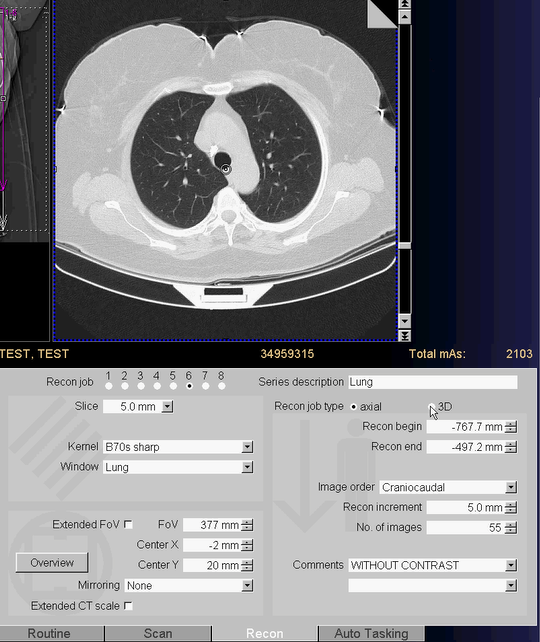

- اصول Reconstruction در سي تي اسكن Siemens و Philips

- كاربرد هر بخش موجود در تب Reconstruction در سي تي اسكن Siemens و Philips

- كاربرد كرنل و فيلتر در هر آزمون كلينيكال سي تي اسكن